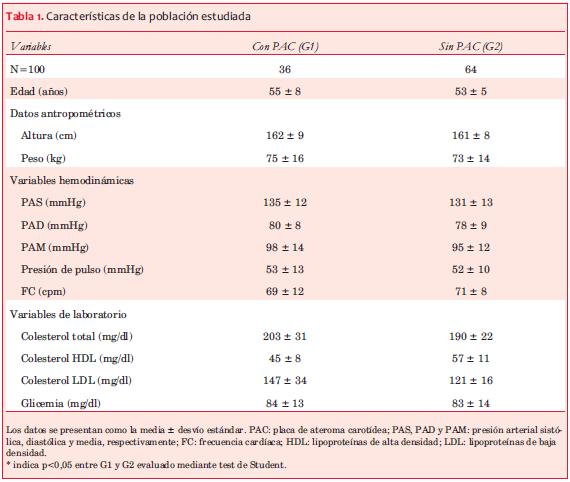

Las medidas antropométricas, hemodinámicas y de laboratorio se detallan en la tabla 1.

No se observaron diferencias significativas en la edad ni en las medidas antropométricas de los sujetos con y sin PAC. La PA sistólica, PA diastólica, presión de pulso y FC fueron similares entre los grupos estudiados. Los niveles de colesterol total y fracción de lipoproteínas de baja densidad (LDL) fueron superiores en G1 (con PAC) respecto al G2 (sin PAC), mientras que los niveles de la fracción de lipoproteínas de alta densidad (HDL) fueron inferiores en el G1 (p<0,05). No hubo diferencias significativas en la glicemia de ayuno entre los grupos.

Se incluyeron 71 PAC (G1), de las cuales 35 se clasificaron como lipídicas, 16 como fibrolipídicas y 20 con contenido mayoritariamente fibroso/calcificado (tabla 2). Todas las PAC incluidas presentaban entre 15% y 45% de estenosis luminal, sin compromiso significativo del flujo arterial.